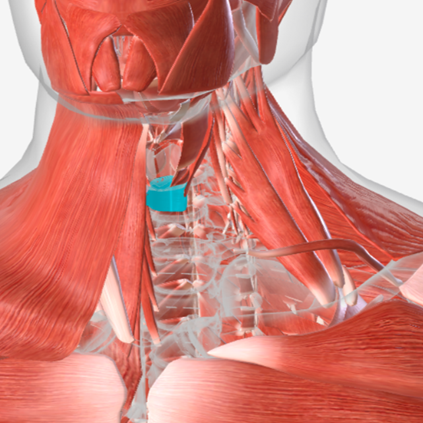

Inferior pharyngeal constrictor

origin is the oblique line of the thyroid laminae, coursing up and back to insert on the median pharyngeal raphe; function is to reduce the diameter of the lower pharynx

Inferior Pharyngeal Constrictor

|  |  |

Inferior pharyngeal constrictor

E

Inferior pharyngeal constrictor

E

Inferior pharyngeal constrictor

H